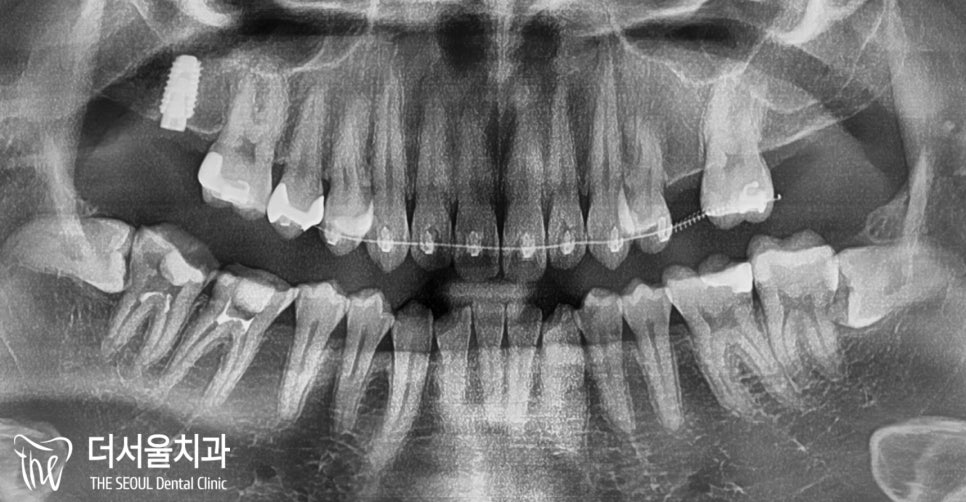

진료 전, 촬영했던 파노라마 엑스레이를 보면

공간 협소 외에는 별다른 문제는 없었습니다.

왼쪽에 작은 어금니 하나가 비었죠?

25번 어금니를 상실해 있습니다.

교합면을보면 뭔가 좁다는 느낌을 받을 수 있는데,

치아를 상실한지 조금 오래 되었다 하셨습니다.

그래서 25번 위치는 픽스처를 식립하기

힘든 상태였습니다.